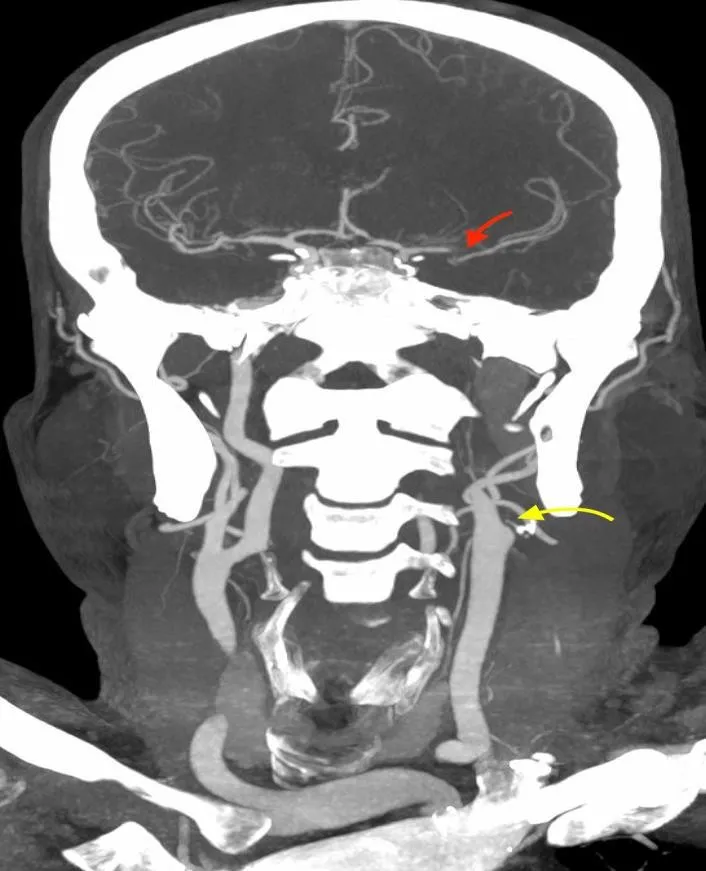

Рисунок 2. Результати МСКТ-ангіографії церебральних судин.

Результати МСКТ-ангіографії (ліворуч коронарна, праворуч – аксіальна MIP-реконструкція) свідчили про оклюзію лівої внутрішньої сонної артерії (ВСА) в екстракраніальному сегменті

(жовта стрілка) та оклюзію лівої середньої мозкової артерії (СМА) в сегменті М1 (червоні стрілки).